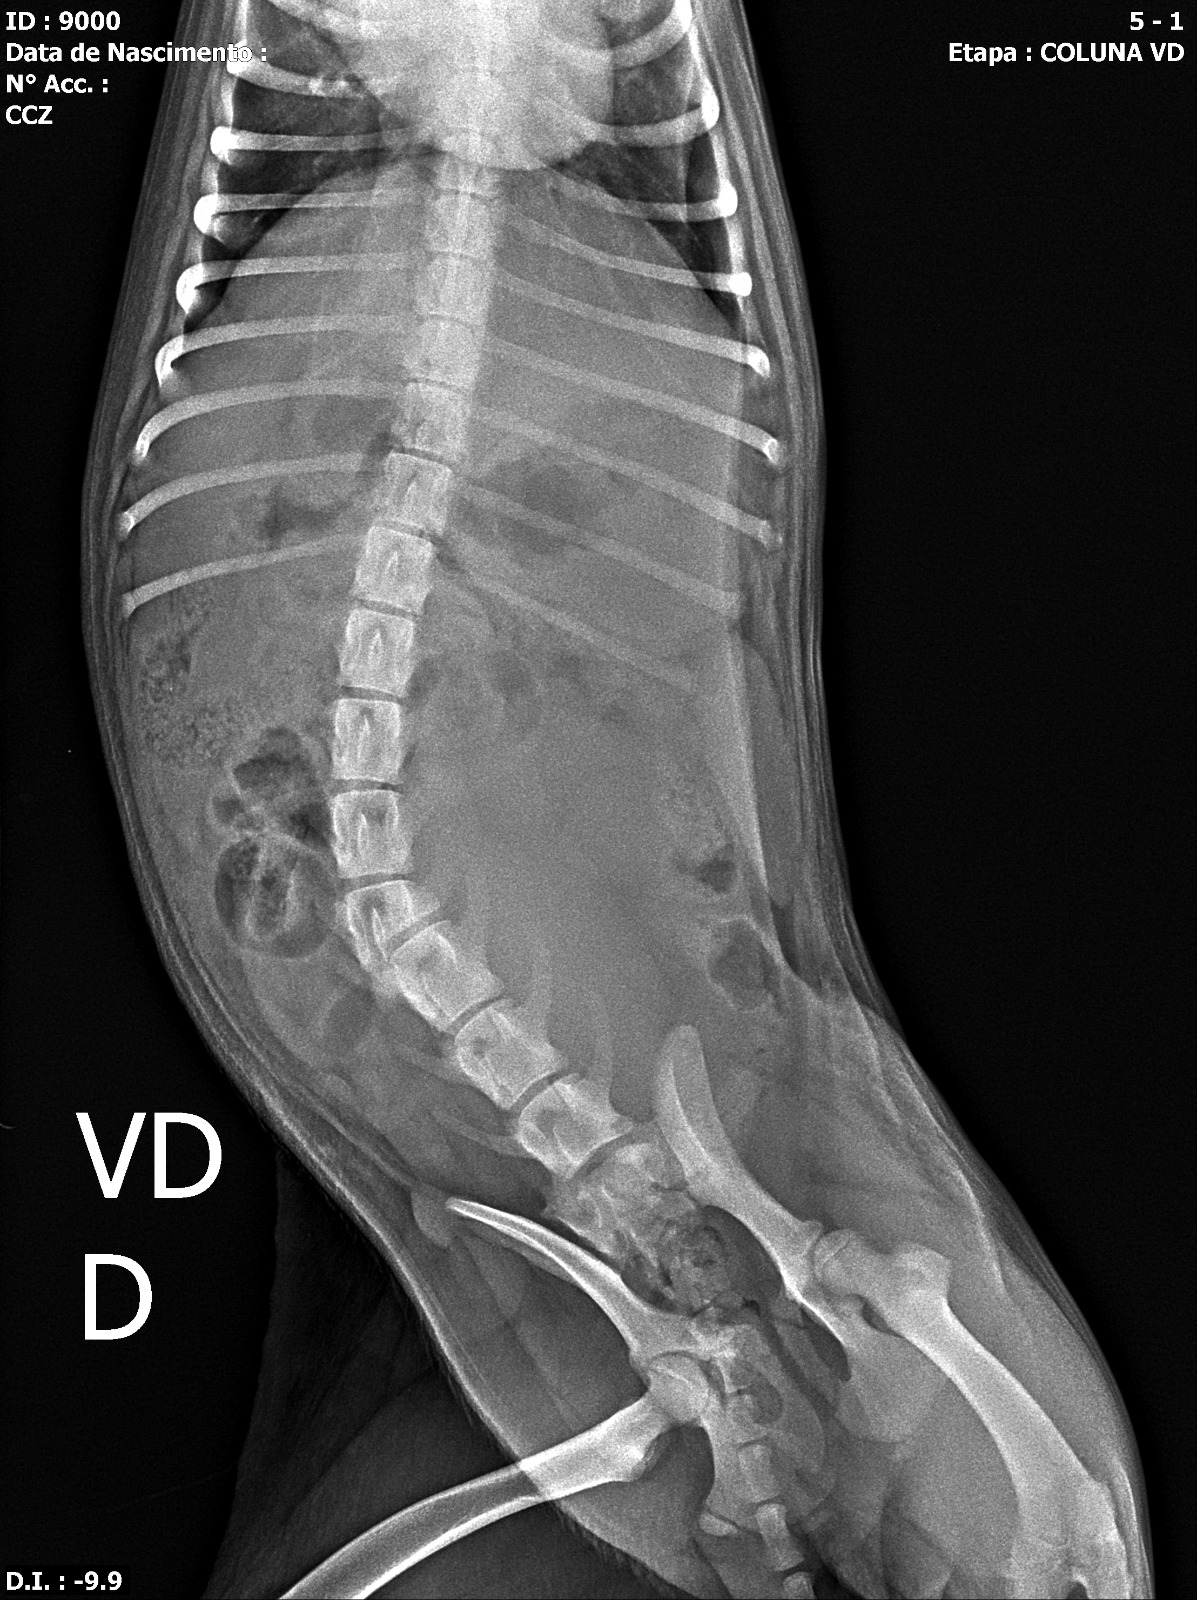

De acordo com atualização publicada no perfil do parlamentar, a cadela apresenta lesão medular associada a fratura toracolombar com instabilidade vertebral, quadro que resultou na perda dos movimentos das patas traseiras.